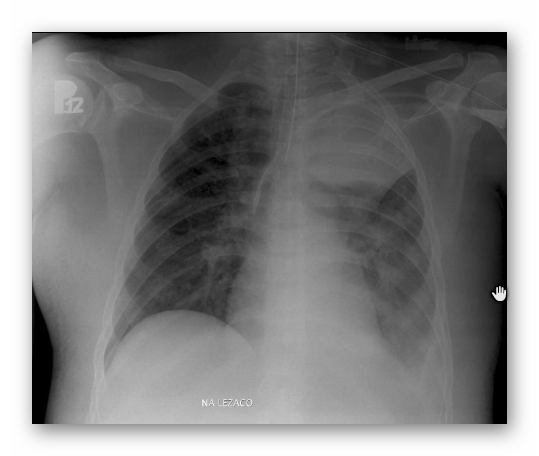

OBRZĘK PŁUC

RTG